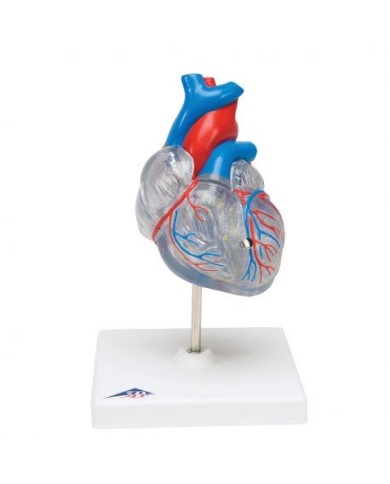

I modellini anatomici di cuore umano sono strumenti indispensabili per uno studio corretto dell'anatomia del cuore umano.

Su Tuttoanatomia trovi la più vasta selezione online, certamente abbiamo il modello di cuore più adatto alle tue esigenze. I cardiologi e gli studenti acquistano i modelli anatomici di cuore umano per studiare nei minimi dettagli la struttura anatomica del cuore umano, ma anche per dare spiegazioni ai propri pazienti, per illustrare visivamente la patologia di cui sono affetti, ed il tipo di intervento che si intende eseguire durante la terapia. Le quotazioni su Tuttoanatomia sono le più convenienti del mercato e la qualità dei prodotti è davvero eccezionale, in modo da offrirti un rapporto qualità prezzo incomparabile.